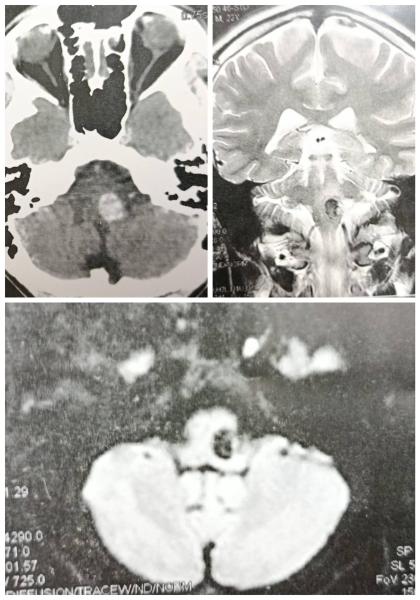

​في سبق طبي جديد يؤكد ريادة مستشفيات جامعة أسيوط، نجح فريق طبي متخصص بقسم جراحة المخ والأعصاب، في إجراء واحدة من أدق وأخطر الجراحات الميكروسكوبية، باستئصال ورم وعائي (وحمة دموية - Cavernoma) من "جذع المخ" لشاب، وهي المنطقة التي تُعرف طبياً بأنها أكثر مناطق الجهاز العصبي حساسية، جاء هذا الإنجاز الطبي تحت رعاية الأستاذ الدكتور أحمد المنشاوي، رئيس الجامعة، والأستاذ الدكتور علاء عطية، عميد كلية الطب ورئيس مجلس إدارة المستشفيات الجامعية، والأستاذ الدكتور محمد السيد، رئيس قسم جراحة المخ والأعصاب.

قد استقبل شاب يبلغ من العمر (٢٣)، يعاني من وحمة دموية من جذع مخ، تسببت له بأعراض عصبية متعددة شملت صداع شديد، واضطراب في الاتزان، وضعفا بالأطراف، وتأثر ببعض الأعصاب المخية، وتكمن صعوبة العملية في الموقع التشريحي للورم، حيث يعتبر جذع المخ الممر الرئيسي لمراكز التحكم في التنفس، الحركة، الاتزان، والأعصاب المخية، وهو ما يجعل التدخل الجراحي في هذه المنطقة بالغ الخطورة، نظرًا لأن أي خطأ غير مقصود قد يؤدي إلى مضاعفات دائمة.